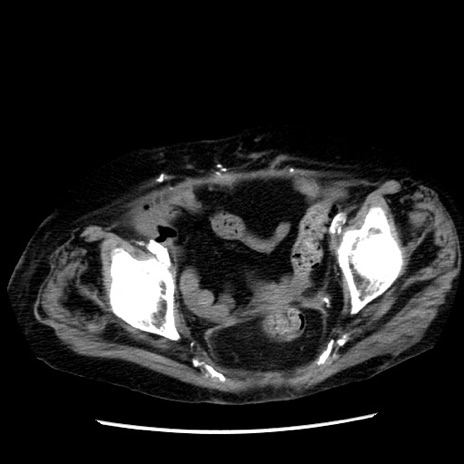

冠状断像

症例14(横断像)

【症例】 90歳代女性

【主訴】 腹痛・嘔吐

【現病歴】今朝から左側腹部痛を認めた。 経過観察していたが、嘔吐を認めたため来院。

【既往歴】 子宮癌術後

【身体所見】 意識清明、BP 127/54mmHg、P 98bpm Sp02 95%(RA)、BT 35.8°C、腹部平坦・軟腸ぜん動音聴取良好、右下腹部圧痛(+) 反跳痛なし

【データ】WBC 9800、CRP 0.46